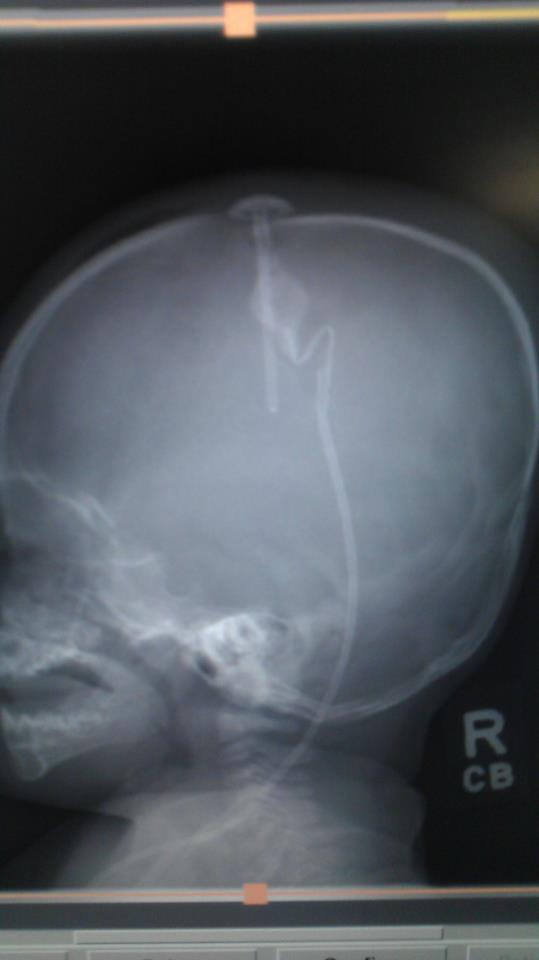

Xavier was doing super well this morning and we noticed a huge improvement over how he’d been over the past few weeks. They did a CT Scan and X-rays and the surgeon came in to talk to us before being released. As you can see on the X-ray, his shunt has a sharp bend in the catheter which they were afraid might pinch and cause the shunt to stop working. He was showing no negative signs, so they released us and scheduled a follow up visit after Christmas to do another operation to fix the catheter so it doesn’t have the bend. (I asked that we get this in before the new year so we don’t get hit with our huge deductible). So we came home and Xavier has gotten worse as the night went on. He has a fever, is irritable, and has been vomiting. So we are heading back to Primary Childrens in the morning where they will likely do the surgery tomorrow to fix the kink.

Some of you have asked how the shunt works, and in the X-ray you can see the shunt that goes down into the ventricle in the brain, the round valve which releases when pressure builds, and the catheter that goes behind his ear and down into his abdomen to drain the cerebral fluid. (I could now give lectures on VP shunts… I would just need a handy-dandy laser pointer)